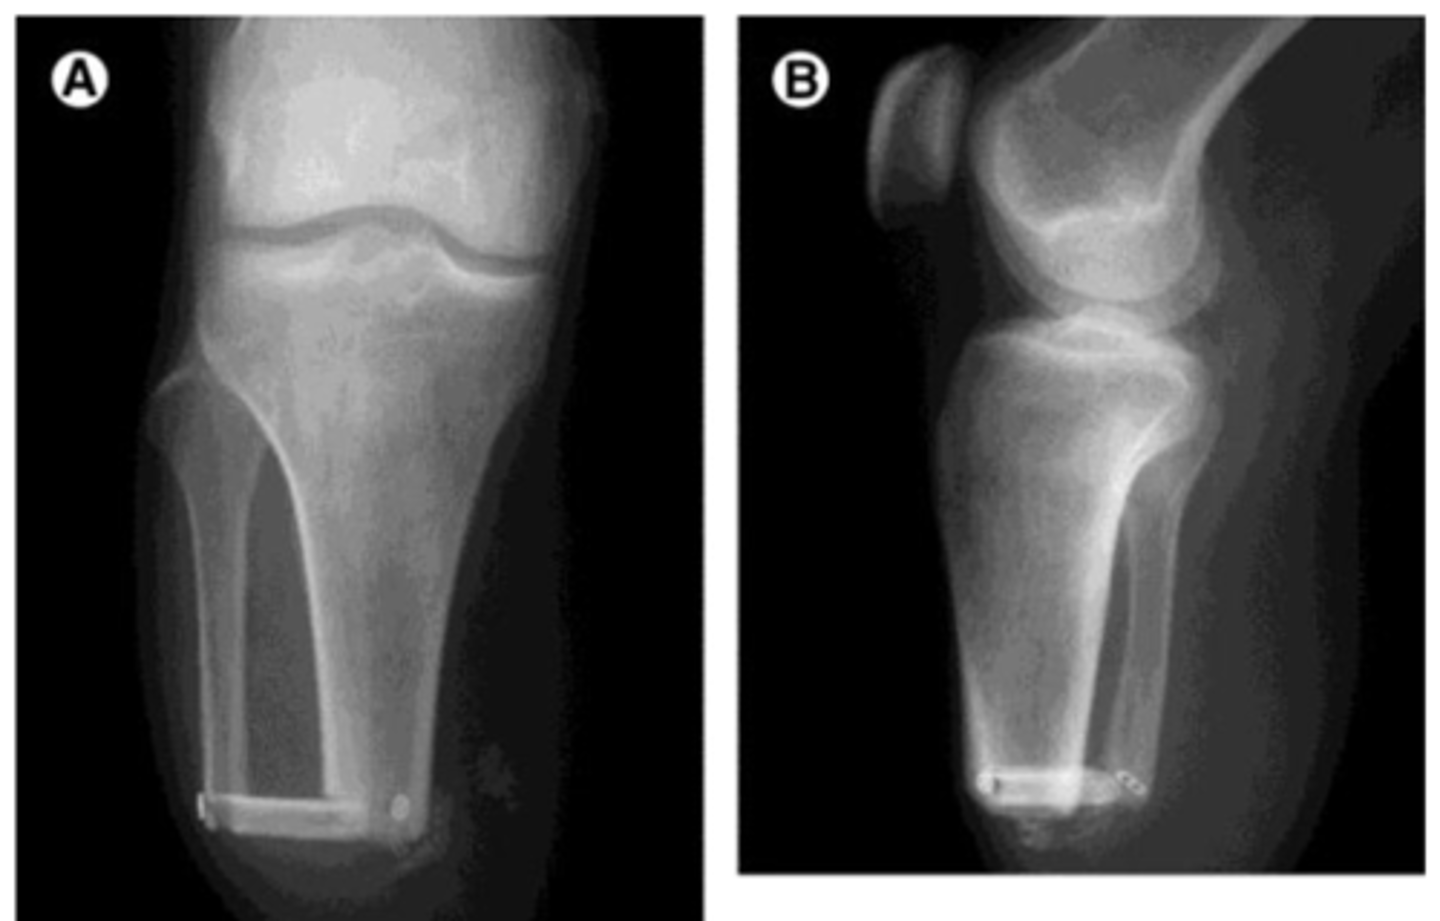

This procedure is a modification of a transtibial wherein the fibula is cut to same length as the tibia and bone (or metal) and a bridge is placed to allow distal end WBing; little evidence to support benefit

ERTL procedure (Still need a prosthetic but helps create a little more structure)

The ERTL procedure is good for patients who have potential to be highly (active/inactive)